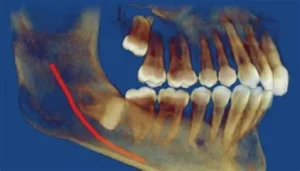

An impacted tooth is a common dental issue that occurs when a tooth fails to emerge properly from the gum line. It is most often